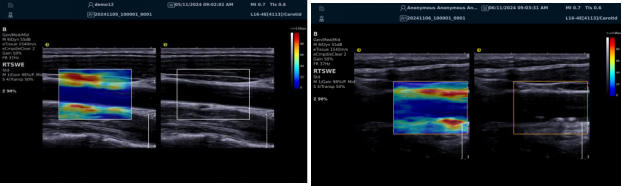

(一)RTSWE 实时剪切波弹性成像技术

RTSWE 技术源于对剪切波的创新研究,通过 MultiPush?超声触诊技术产生振动生成剪切波,OmniSound?平台提升帧频捕获信息并测量杨氏模量。其优势突出:

? 可视化,对颈动脉内膜和斑块实时弹性成像,彩色编码显示硬度,便于医生区分斑块类型。

? 定量测量方面,分析结果以kPam/s为单位测量颈动脉相关部位杨氏模量,毫米级分辨率显示微小病变,提供 20 余种参数综合评估斑块稳定性和血管硬化因测量取样范围可极度小甚至对于颈动脉内中膜硬度可定量测量,引发不同视角评价极早期动脉硬化评估,实属科研利器。

? 采用马赫圆锥脉冲激励技术,无需按压,减少检查者影响,帧频高、操作简便、耗时短。

RTSWE 是全球唯一的实时全幅全定量剪切波弹性成像系统,OmniSound?平台采集与显示帧频国际领先,对颈动脉结构定量分析和脑卒中早期预防意义重大。